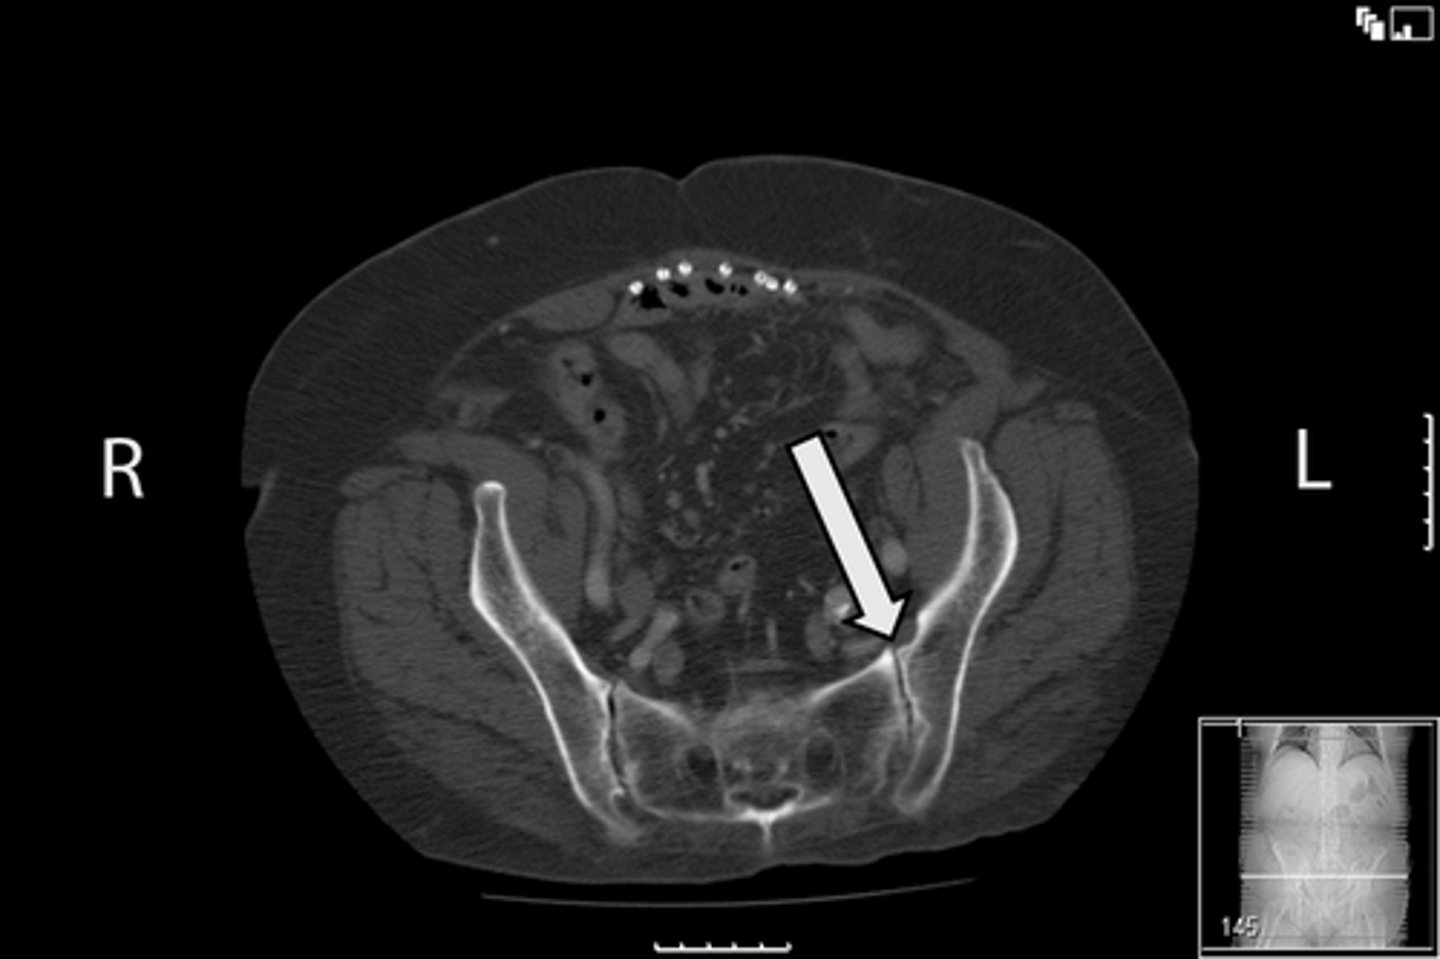

Axial bony pelvis CT

What is the image?

32

L ilium

<p>What is indicated in the image?</p>

New cards

What is indicated in the image?

34

R ilium

36

Sacrum